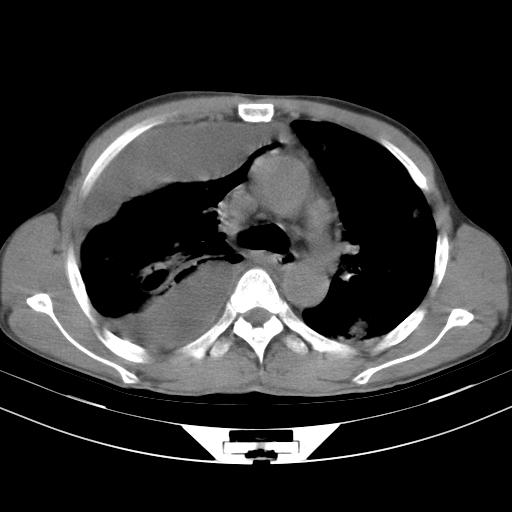

男性,44岁,结核病史多年。现胸闷气短,咳嗽,偶咳血。

右侧胸腔积液

右肺下叶不张

双肺多发结节影最分空洞形成考虑占位不除外结核

双肺陈旧性病变

1、右侧大量胸腔积液伴右肺压缩性膨胀不全,建议抽液治疗后复查 2、两肺继发性tb伴空洞形成。

1)两肺继发性肺结核伴空洞形成,左肺多发性结核球。2)右侧大量胸腔积液伴右肺部分膨胀不全。3)纵隔淋巴结肿大。

1,双肺多发结节 并空洞影改变, 左侧胸腔积液并部分包裹, 结合原病史首先考虑结核. 但也不除外其它.

2,左侧有一根肋骨陈旧性骨折? 建议追查 .

吉大一院胸水抽检结果:结核性胸水